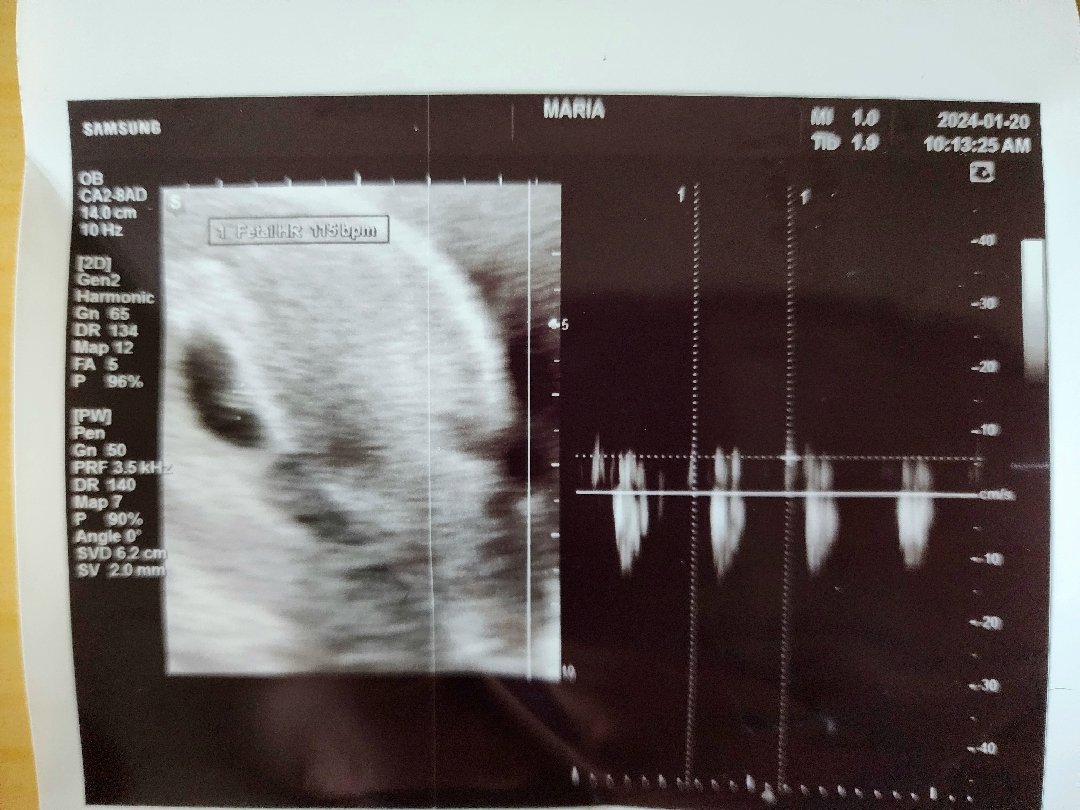

첫 심장소리 듣고왔어요!

6주 4일차, 첫 심소 듣고왔어요. 이럴수가.. 제 안에서 두 심장이 뛴다는게 이런 기분이군요.ㅜㅜ🥹 평소 눈물이 많은 편이지만, 지난 초음파에서 아기집 확인할 땐 얼떨떨해서 안 울었는데 이번엔 심장소리 들으니 저도 모르게 눈물이 쪼르륵ㅜㅜ🥲 그나저나, 여러분. 꼭 초음파 보기 전엔 소변 비우고 가세요.. 예전에 초음파 잘 보려면 화장실 갔다가랬는데, 진료 대기가 엄청 긴데다 곧 부를 것 같아서 참고 갔더니 질초음파론 아가가 잘 안보이더라고요😂 배초음파로도 왠지 안보이는 듯한ㅋㅋㅋ 꼭 장실 갔다가세요ㅋㅋ